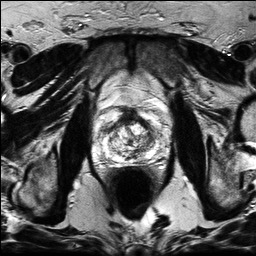

Denoising diffusion probabilistic models (DDPMs) have achieved unprecedented success in computer vision. However, they remain underutilized in medical imaging, a field crucial for disease diagnosis and treatment planning. This is primarily due to the high computational cost associated with (1) the use of large number of time steps (e.g., 1,000) in diffusion processes and (2) the increased dimensionality of medical images, which are often 3D or 4D. Training a diffusion model on medical images typically takes days to weeks, while sampling each image volume takes minutes to hours. To address this challenge, we introduce Fast-DDPM, a simple yet effective approach capable of improving training speed, sampling speed, and generation quality simultaneously. Unlike DDPM, which trains the image denoiser across 1,000 time steps, Fast-DDPM trains and samples using only 10 time steps. The key to our method lies in aligning the training and sampling procedures. We introduced two efficient noise schedulers with 10 time steps: one with uniform time step sampling and another with non-uniform sampling. We evaluated Fast-DDPM across three medical image-to-image generation tasks: multi-image super-resolution, image denoising, and image-to-image translation. Fast-DDPM outperformed DDPM and current state-of-the-art methods based on convolutional networks and generative adversarial networks in all tasks. Additionally, Fast-DDPM reduced training time by a factor of 5 and sampling time by a factor of 100 compared to DDPM. Our code is publicly available at: https://github.com/mirthAI/Fast-DDPM.